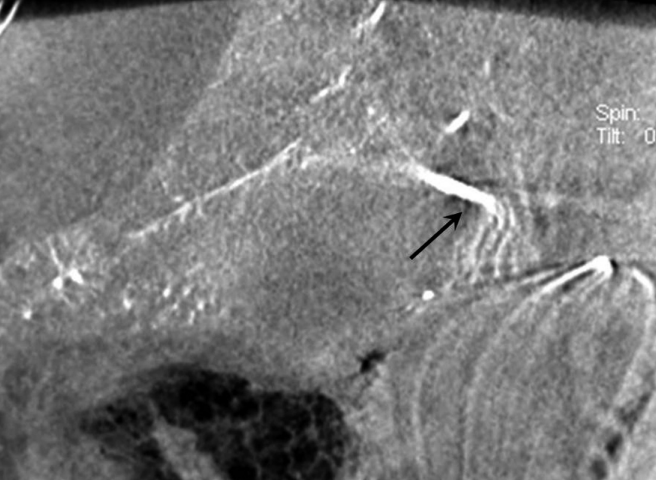

복강동맥조영술에서 우간동맥의 분지부에 인접한 위치에 가성동맥류를 확인하였다(Fig. 2A, B). 6F Shuttle guiding catheter(Cook, Bloomington, IN, USA)로 교체 후에 Stent-graft(4×26mm, JoStent GraftMaster®, JoMed, Germany)를 가성동맥류가 있는 우간동맥에 위치시키고, 풍선카테터(Ultra-thin Diamond,Boston Scientific, Galway, Ireland)를 사용하여 확장시켰다. 시술 직후 시행한 복강동맥조영술에서 동맥류는 관찰되지 않았다(Fig. 2C).

Fig. 2

Celiac (A) and hepatic angiogram (B) show the pseudoaneurysm (arrows in A and B) at distal part of the right hepatic artery near the origin of the right posterior hepatic artery. (C) On hepatic angiogram after stent-graft placement (arrow), the pseudoaneurysm is completely excluded.